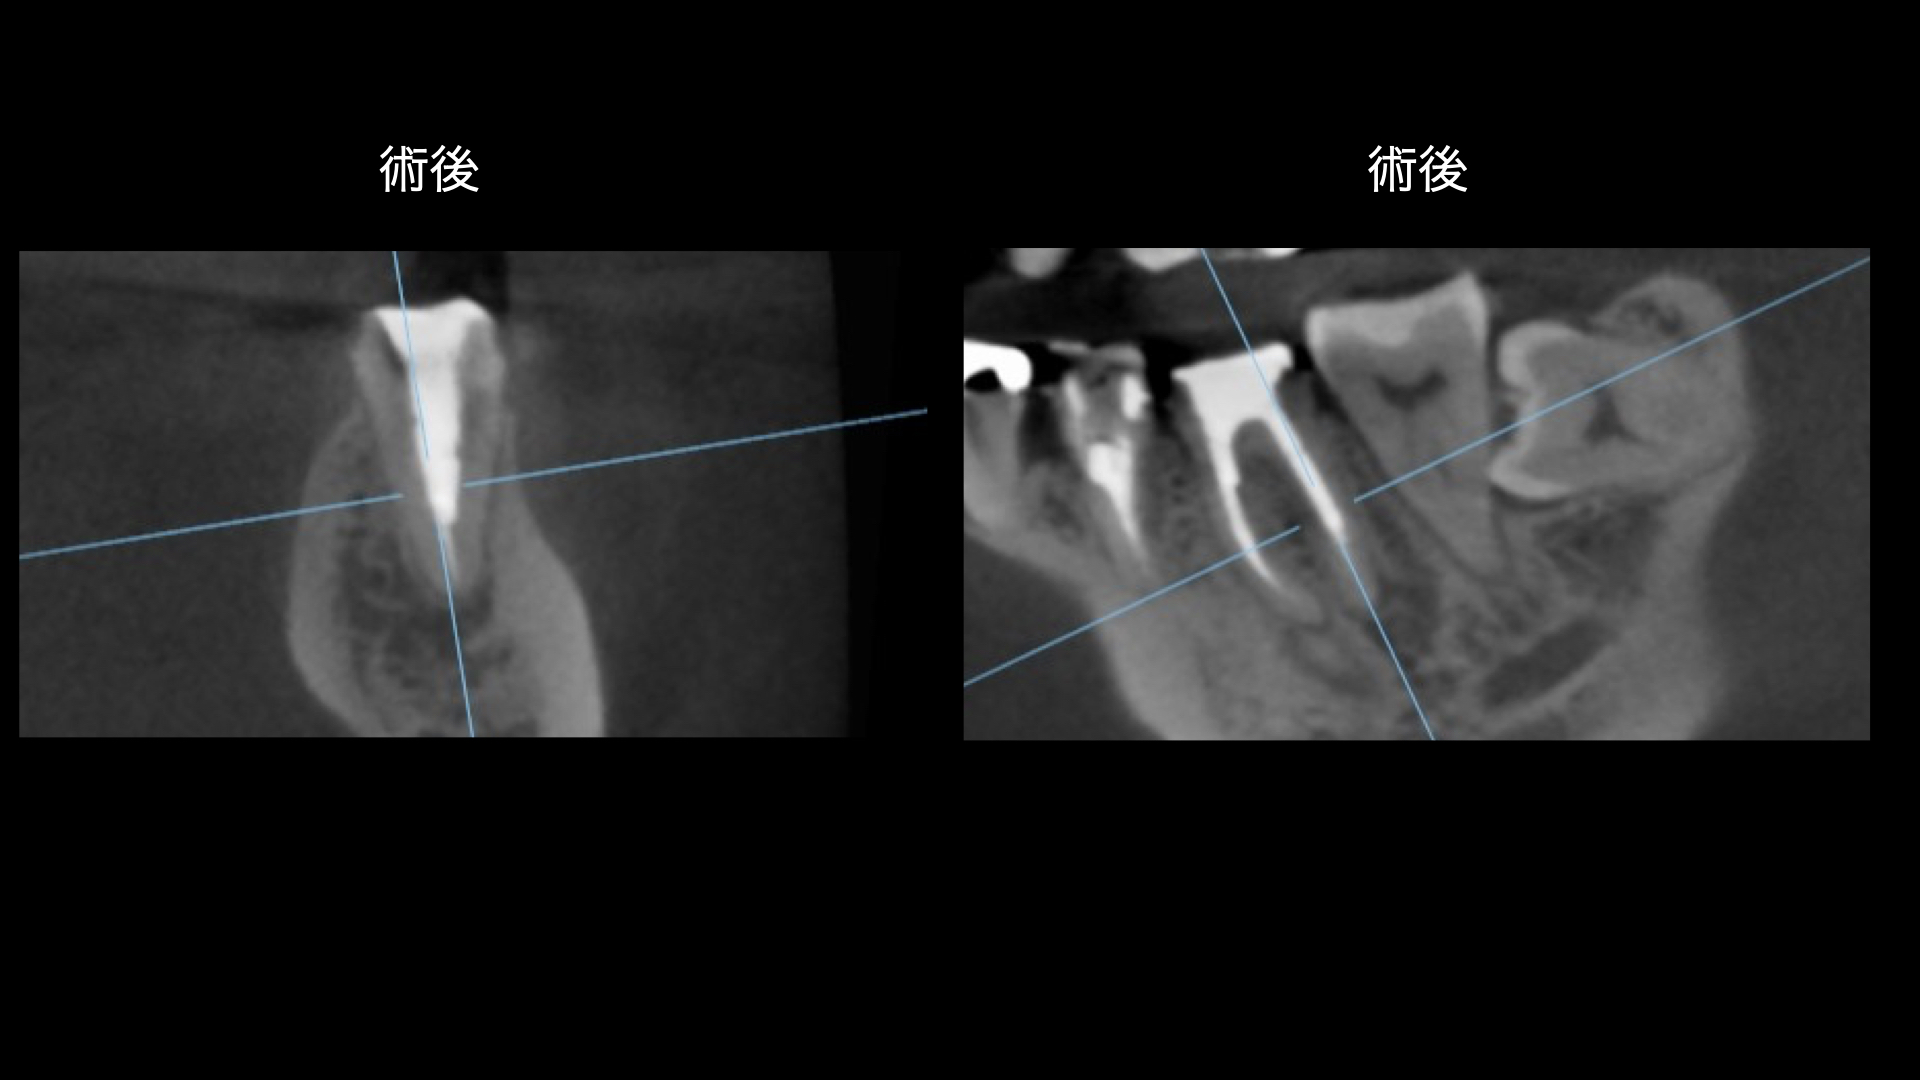

術前・術後 比較(根管充填より6ヶ月)

精密根管治療後の経過観察において、噛んだ際の違和感や歯ぐきからの排膿は消失し、症状は安定して推移しています。術後のCT検査では、治療前に認められていた根尖部の大きな透過像(骨吸収像)が縮小し、周囲の骨の回復傾向が確認されました。湾曲の強い根管であったものの、マイクロスコープ下で精密に感染源を除去・封鎖することで、良好な治癒反応が得られています。